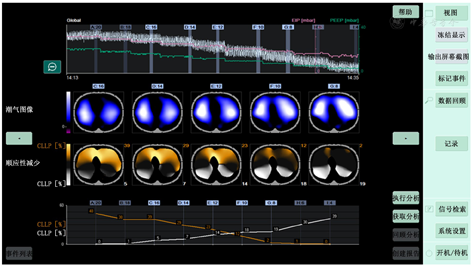

电阻抗断层成像(electrical impedance tomography,EIT)是一种无辐射、可视化的床旁无创、连续、动态监测肺部区域通气及灌注的功能成像技术,其原理是通过局部电极对胸腔施加微弱电流而计算出胸腔变化的生物电阻,进而利用相应算法成像来监测胸腔功能状态[1](图1)。EIT对于胸部功能(如肺区域通气、呼吸系统顺应性及区域灌注等)的评估被认为是有临床意义的[2],可以有效地进行动态评估和指导临床决策,具有重要的临床价值。本文依据新的循证医学证据结合临床应用经验,探讨EIT在ICU不同场景下的应用价值并进行展望。

注:EIT为电阻抗断层成像;B图分为4个感兴趣区域,分别为感兴趣区1、感兴趣区2、感兴趣区3、感兴趣区4,一般1、2区可反映非重力依赖区通气情况,3、4区可反映重力依赖区通气情况

ARDS是急性呼吸衰竭的一个重要原因,通常与多器官功能衰竭有关,其特点是血管通透性增加造成的肺水肿、严重的低氧血症和二氧化碳弥散障碍。大量临床研究显示应用肺保护性通气时,患者生存率得到了提高。严重ARDS的肺保护性通气策略包括:小潮气量、合适的PEEP和俯卧位通气等。数据表明,与大潮气量相比4~8 ml/kg的小潮气量,并保持平台压<30 cmH2O(1 cmH2O=0.098 kPa)是可以降低病死率的[11]。同时,俯卧位通气也是改善严重ARDS患者氧合的成熟方法并可降低病死率[12],而PEEP的设置仍不确定,PEEP虽有助于肺泡复张,防止肺泡塌陷,达到改善氧合、减少肺部应力和应变的目的,但同时也有一些潜在风险,有可能会造成肺泡过度膨胀导致损伤,增加肺内分流、死腔和血管阻力。虽然没有严格定义什么是较高PEEP与较低PEEP,但大多数研究已证实与较低PEEP相比,较高PEEP治疗的病死率相对较低。此外,不适当的高PEEP可能会导致肺损伤的发生,所以个体化的PEEP设置一直是ARDS患者机械通气所面临的难题。EIT的应用似乎是近几年滴定PEEP研究的热点,其中区域顺应性评估过度膨胀和塌陷主要是通过EIT计算出不同PEEP水平的塌陷率和过度膨胀率,根据塌陷与过度膨胀率选择和指导"最佳PEEP",进而防止肺泡塌陷和过度膨胀(图2)。作为一种无创、无辐射、可视化、动态评估设备相较于传统ARDSnet(急性呼吸窘迫综合征协作网)滴定PEEP的方法明显减少了整体肺组织弥漫性损伤(水肿、炎症)[13]。较传统准静态压力-容积(pressure-volume,P-V)曲线滴定PEEP策略相比,EIT应用顺应性评估过度膨胀和塌陷的方法指导滴定PEEP可改善氧合及顺应性,降低驱动压和病死率[14]。而对于肺异质性较高的ARDS来说"呼吸钟摆"现象会加重其肺损伤的发生,因此,指导区域性肺通气显得尤为重要,Scaramuzzo等[15]研究中提到在肺源性ARDS中EIT指导的PEEP值比跨肺压指导的要低,同时可使吸气末跨肺压明显降低且通气分布更均匀;而肺外源性ARDS患者中EIT建议应用更高的PEEP值,从而获得更好的重力依赖区通气分布,但呼吸系统驱动压和跨肺压略高。目前基于EIT滴定PEEP的方法有很多,除上述顺应性评估过度膨胀和塌陷方法外,总体不均一指数(global inhomogeneity index,GI)也是应用较广且安全可行的方法之一[16]。笔者团队结合EIT临床应用经验将两种方法作为PEEP滴定的共同参考指标,患者临床获益明显。